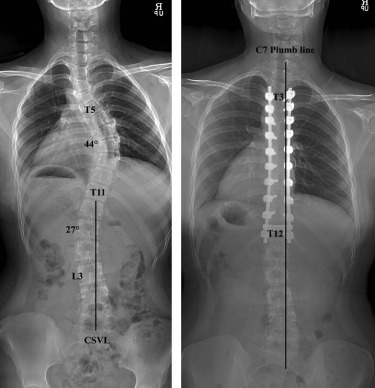

척추가 이렇게 휘게 되면 일상생활에 지장이 없는 경우는 많습니다. 하지만 만곡이 심해지는 경우 심폐합병증이 가장 치명적이고 무서운 합병증이 될 수 있습니다. 일단 기본적으로 whole spine X-ray 를 촬영하여 척추의 pedicle 의 회전과 만곡의 정도를 cubbs angle 등으로 측정을 하게 됩니다.

척추측만증 교정원칙

주만곡을 꼭 모두 유합을 해야하며, 유연성이 있는 보상성 만곡은 유합할 필요가 없습니다.

만곡 상부의 neutral vertebra 부터 하부의 neutral vertebra 까지 유합을 합니다. 따라서 척추체의 회전의 유무가 중요하게 됩니다.

유합의 가장 하단은 stable vertebra 로 sacral central line이 가운데를 지나가도록 해야합니다.

흉추의 후만 및 요추의 전만각은 정상에 가깝게 교정해야합니다.